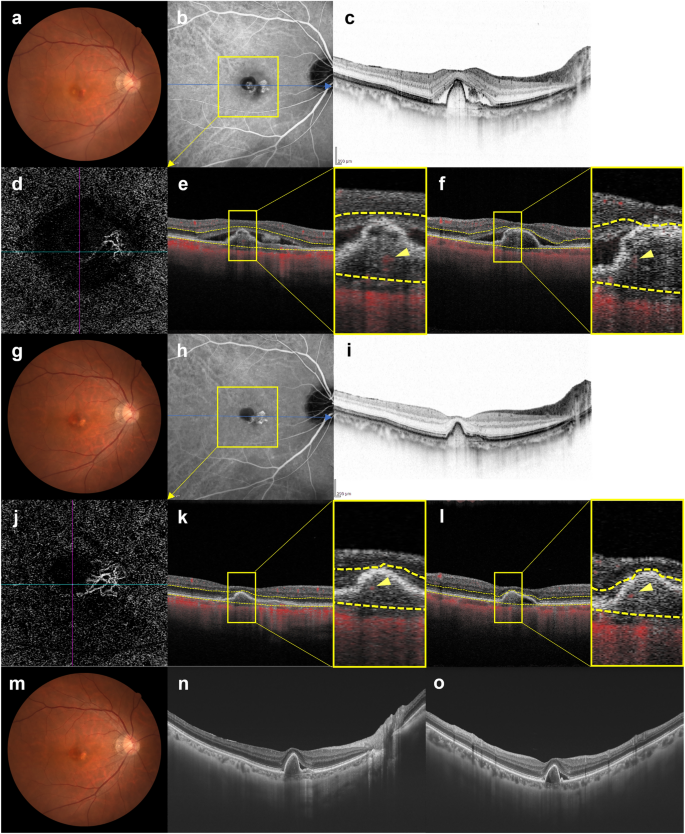

Images of the right eye of a 69-year-old man with polypoidal choroidal vasculopathy in the group showing persistence of blood flow signals within polypoidal lesions. (a–f) Baseline. Best corrected-visual acuity (BCVA) of the right eye is − 0.08 logarithm of the minimal angle of resolution (logMAR) units. (a) Color fundus photograph shows an orange-red lesion accompanied by subretinal hemorrhage. (b) Indocyanine green angiography (ICGA) shows a polypoidal lesion with a branching neovascular network (BVN). (c) Optical coherence tomography (OCT) B-scan image through the fovea shows a sharp-peaked and shallow irregular pigment epithelial detachment (PED) with serous retinal detachment (SRD). (d) Optical coherence tomography angiography (OCTA) en face image shows blood flow signals corresponding to the polypoidal lesion and the BVN. (e, f) OCTA B-scan images (e: horizontal, f: vertical) show blood flow signals within the PED corresponding to the polypoidal lesion (arrowheads). (g–l) 3 months after the initial treatment. BCVA of the right eye is − 0.08 logMAR units. (g) Color fundus photograph shows no subretinal hemorrhage. (h) ICGA shows complete regression of the polypoidal lesion. (i) OCT B-scan shows the sharp-peaked PED to be diminished without SRD. (j) OCTA en face image shows unclear blood flow signals within the polypoidal lesion. (k, l) OCTA B-scan images (k: horizontal, l: vertical) show blood flow signals within the PED corresponding to the polypoidal lesion (arrowheads). (m–o) 6 months after the initial treatment. BCVA of the right eye is − 0.08 logMAR units. (m) Color fundus photograph shows no subretinal hemorrhage. (n, o) OCT B-scan images through the fovea (n: horizontal, o: vertical) show SRD recurrence and an enlargement of the sharp-peaked PED. In total, 8 injections were required during the 1-year study period due to SRD recurrence.